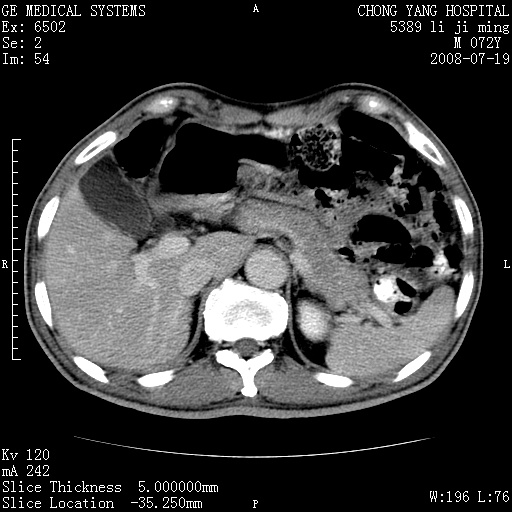

以下是引用zjzjr在2008-7-19 20:57:00的发言:[br]胰头增大,边缘模糊,周围可见渗出影,右侧肾前筋膜增厚.支持胰腺炎.

以下是引用yangyudong333在2008-7-20 6:56:00的发言:[br]胰腺增大尤以胰头明显,边缘模糊,周围可见渗出影,右侧肾前筋膜增厚,肠管於涨.支持胰腺炎

以下是引用不学无术在2008-7-19 23:15:00的发言:[br]胰腺增大尤以胰头明显,边缘模糊,周围可见渗出影,右侧肾前筋膜增厚,肠管於涨.支持胰腺炎